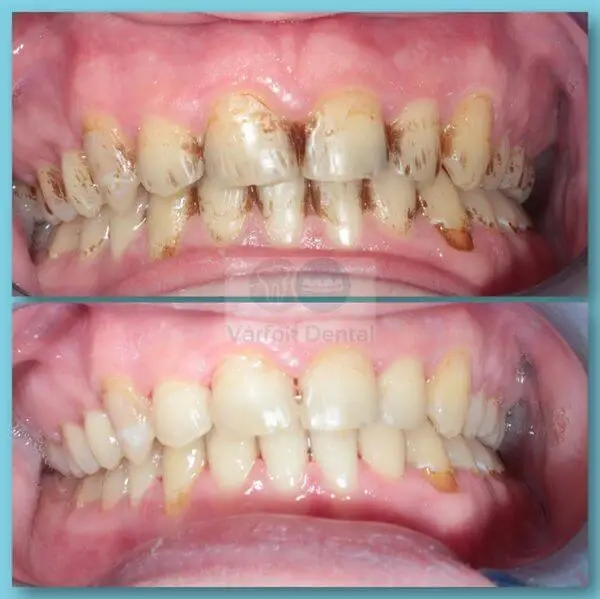

Zárt kürettálás

Páciensünk erősen gyulladt és vérző ínye miatt keresett fel minket. Dr. Erős Roland Ákos egy parodontológiai státuszfelvétel után zárt kürettálással enyhítette a panaszokat.

A megfelelő kezelések hatására meghosszabbodhat a fogak élettartama és az íny ismét szép és egészséges lehet.